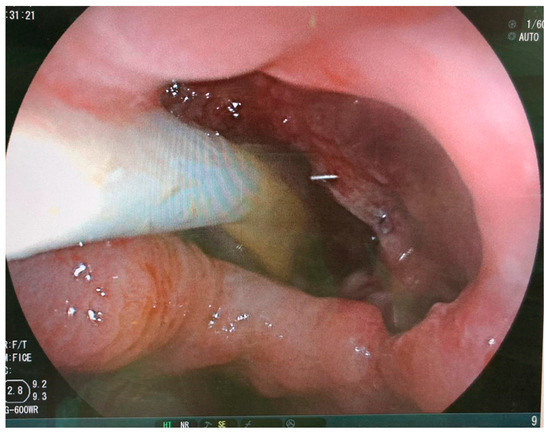

- Dugan, J.; Bajwa, K.; Singhal, S. Endoscopic removal of gastric band by use of a stent-induced erosion technique. Gastrointest. Endosc. 2016, 83, 654–655. [Google Scholar] [CrossRef]

- Manos, T.; Nedelcu, A.; Noel, P.; Zulian, V.; Danan, M.; Vilallonga, R.; Carandina, S.; Nedelcu, M. Endoscopic Gastric Band Removal. J. Clin. Med. 2023, 12, 617. [Google Scholar] [CrossRef] [PubMed]

- Dellaportas, D.; Nastos, C.; Theodosopoulos, T.; Fragulidis, G.; Polydorou, A.; Vezakis, A. Novel Endoscopic Management of Eroding Laparoscopic Adjustable Gastric Band: A Case Series. Case. Rep. Gastrointest. Med. 2018, 2018, 2747852. [Google Scholar] [CrossRef] [PubMed]

- Neto, M.P.; Ramos, A.C.; Campos, J.M.; Murakami, A.H.; Falcao, M.; Moura, E.H.; Evangelista, L.F.; Escalona, A.; Zundel, N. Endoscopic removal of eroded adjustable gastric band: Lessons learned after 5 years and 78 cases. Surg. Obes. Relat. Dis. 2010, 6, 423–427. [Google Scholar] [CrossRef] [PubMed]

- Chisholm, J.; Kitan, N.; Toouli, J.; Kow, L. Gastric band erosion in 63 cases: Endoscopic removal and rebanding evaluated. Obes. Surg. 2011, 21, 1676–1681. [Google Scholar] [CrossRef] [PubMed]

- Di Lorenzo, N.; Lorenzo, M.; Furbetta, F.; Favretti, F.; Giardiello, C.; Boschi, S.; Alfredo, G.; Micheletto, G.; Borrelli, V.; Veneziani, A.; et al. Intragastric gastric band migration: Erosion: An analysis of multicenter experience on 177 patients. Surg. Endosc. 2013, 27, 1151–1157. [Google Scholar] [CrossRef] [PubMed]